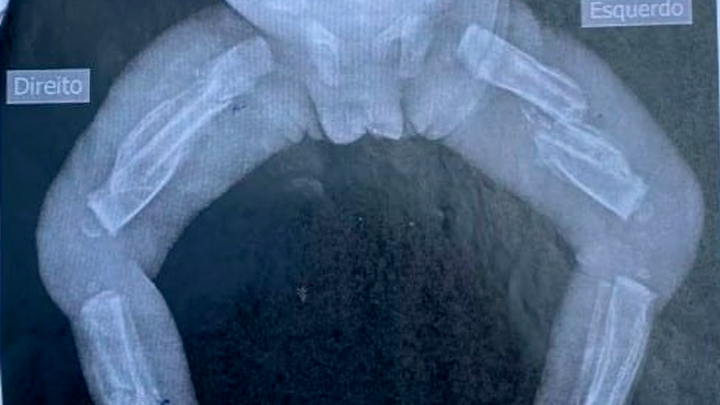

FLORIANÓPOLIS (SC) – Uma mulher de 23 anos foi presa no último domingo (13) suspeita de maltratar a própria filha, uma bebê de apenas 10 meses, em São João Batista, Florianópolis. O caso aconteceu na última sexta-feira (11) e a menina teve as duas pernas, costelas e braços quebrados, além de um roxo no olho e vários hematomas no corpo.

A criança foi atendida no Hospital Monsenhor José Loks, por volta das 19h, onde a equipe médica constatou que ela poderia ter sido arremessada no chão e pisoteada. O Conselho Tutelar foi acionado e descobriu que já existia uma outra denúncia, há aproximadamente 20 dias, sobre a mesma bebê.